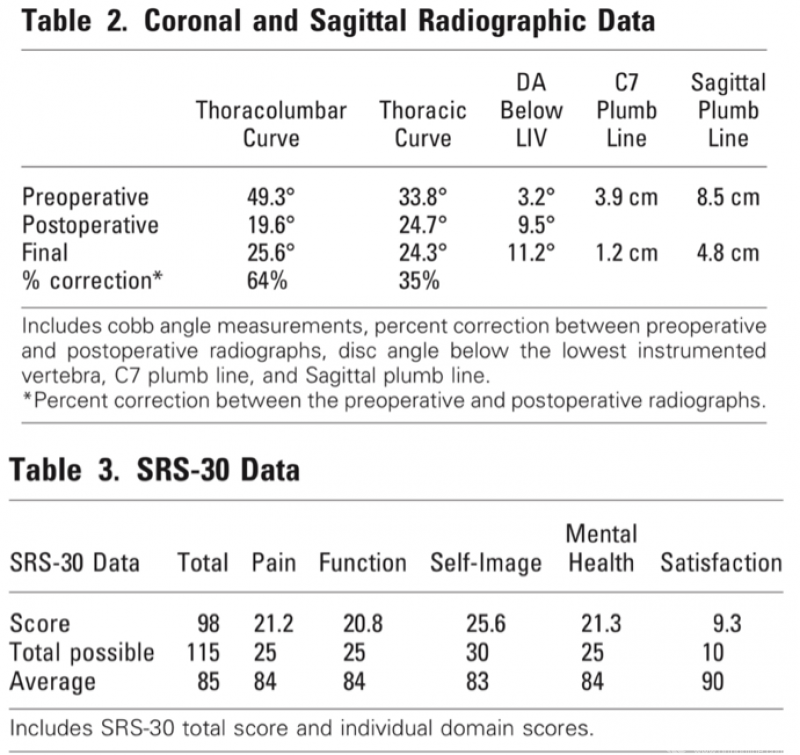

Derek M.等人[6]通过对18例行前路手术的胸腰段/腰段AIS患者进行了平均16.97年(12-22年)的随访发现:前路手术可为胸腰段/腰段AIS患者提供良好的长期功能愈后和稳定的畸形矫正,尽管随访X线显示存在退行性改变,但患者的SRS-30问卷和ODI评分均良好,且行内固定的主弯和自发矫正的代偿性胸弯随时间推移没有发生显著进展。

图5.引文6原文相关数据